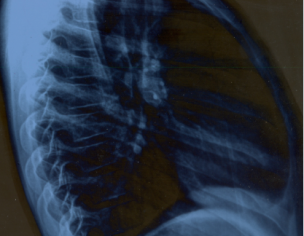

My son ribs bone structure is de-shaping. It's Pectus Carinatum case. Sheikh Zayed Dr. asked to use maximum milk and calcium products in May,2019 but issue is not getting resolved. Kindly advise.

we have to check for ribs and spinal joints. please bring him to us for detailed evaluation and possible treatment

If conservative trial fails then surgery is indicated.